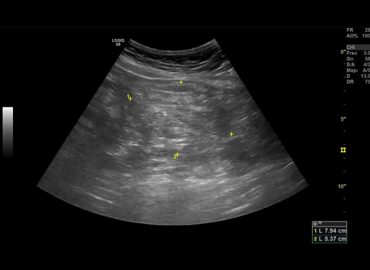

Paciente sexo masculino de 79 años, con antecedentes de HTA y diverticulosis , ingresa por presentar cuadro de lipotimia. Al […]